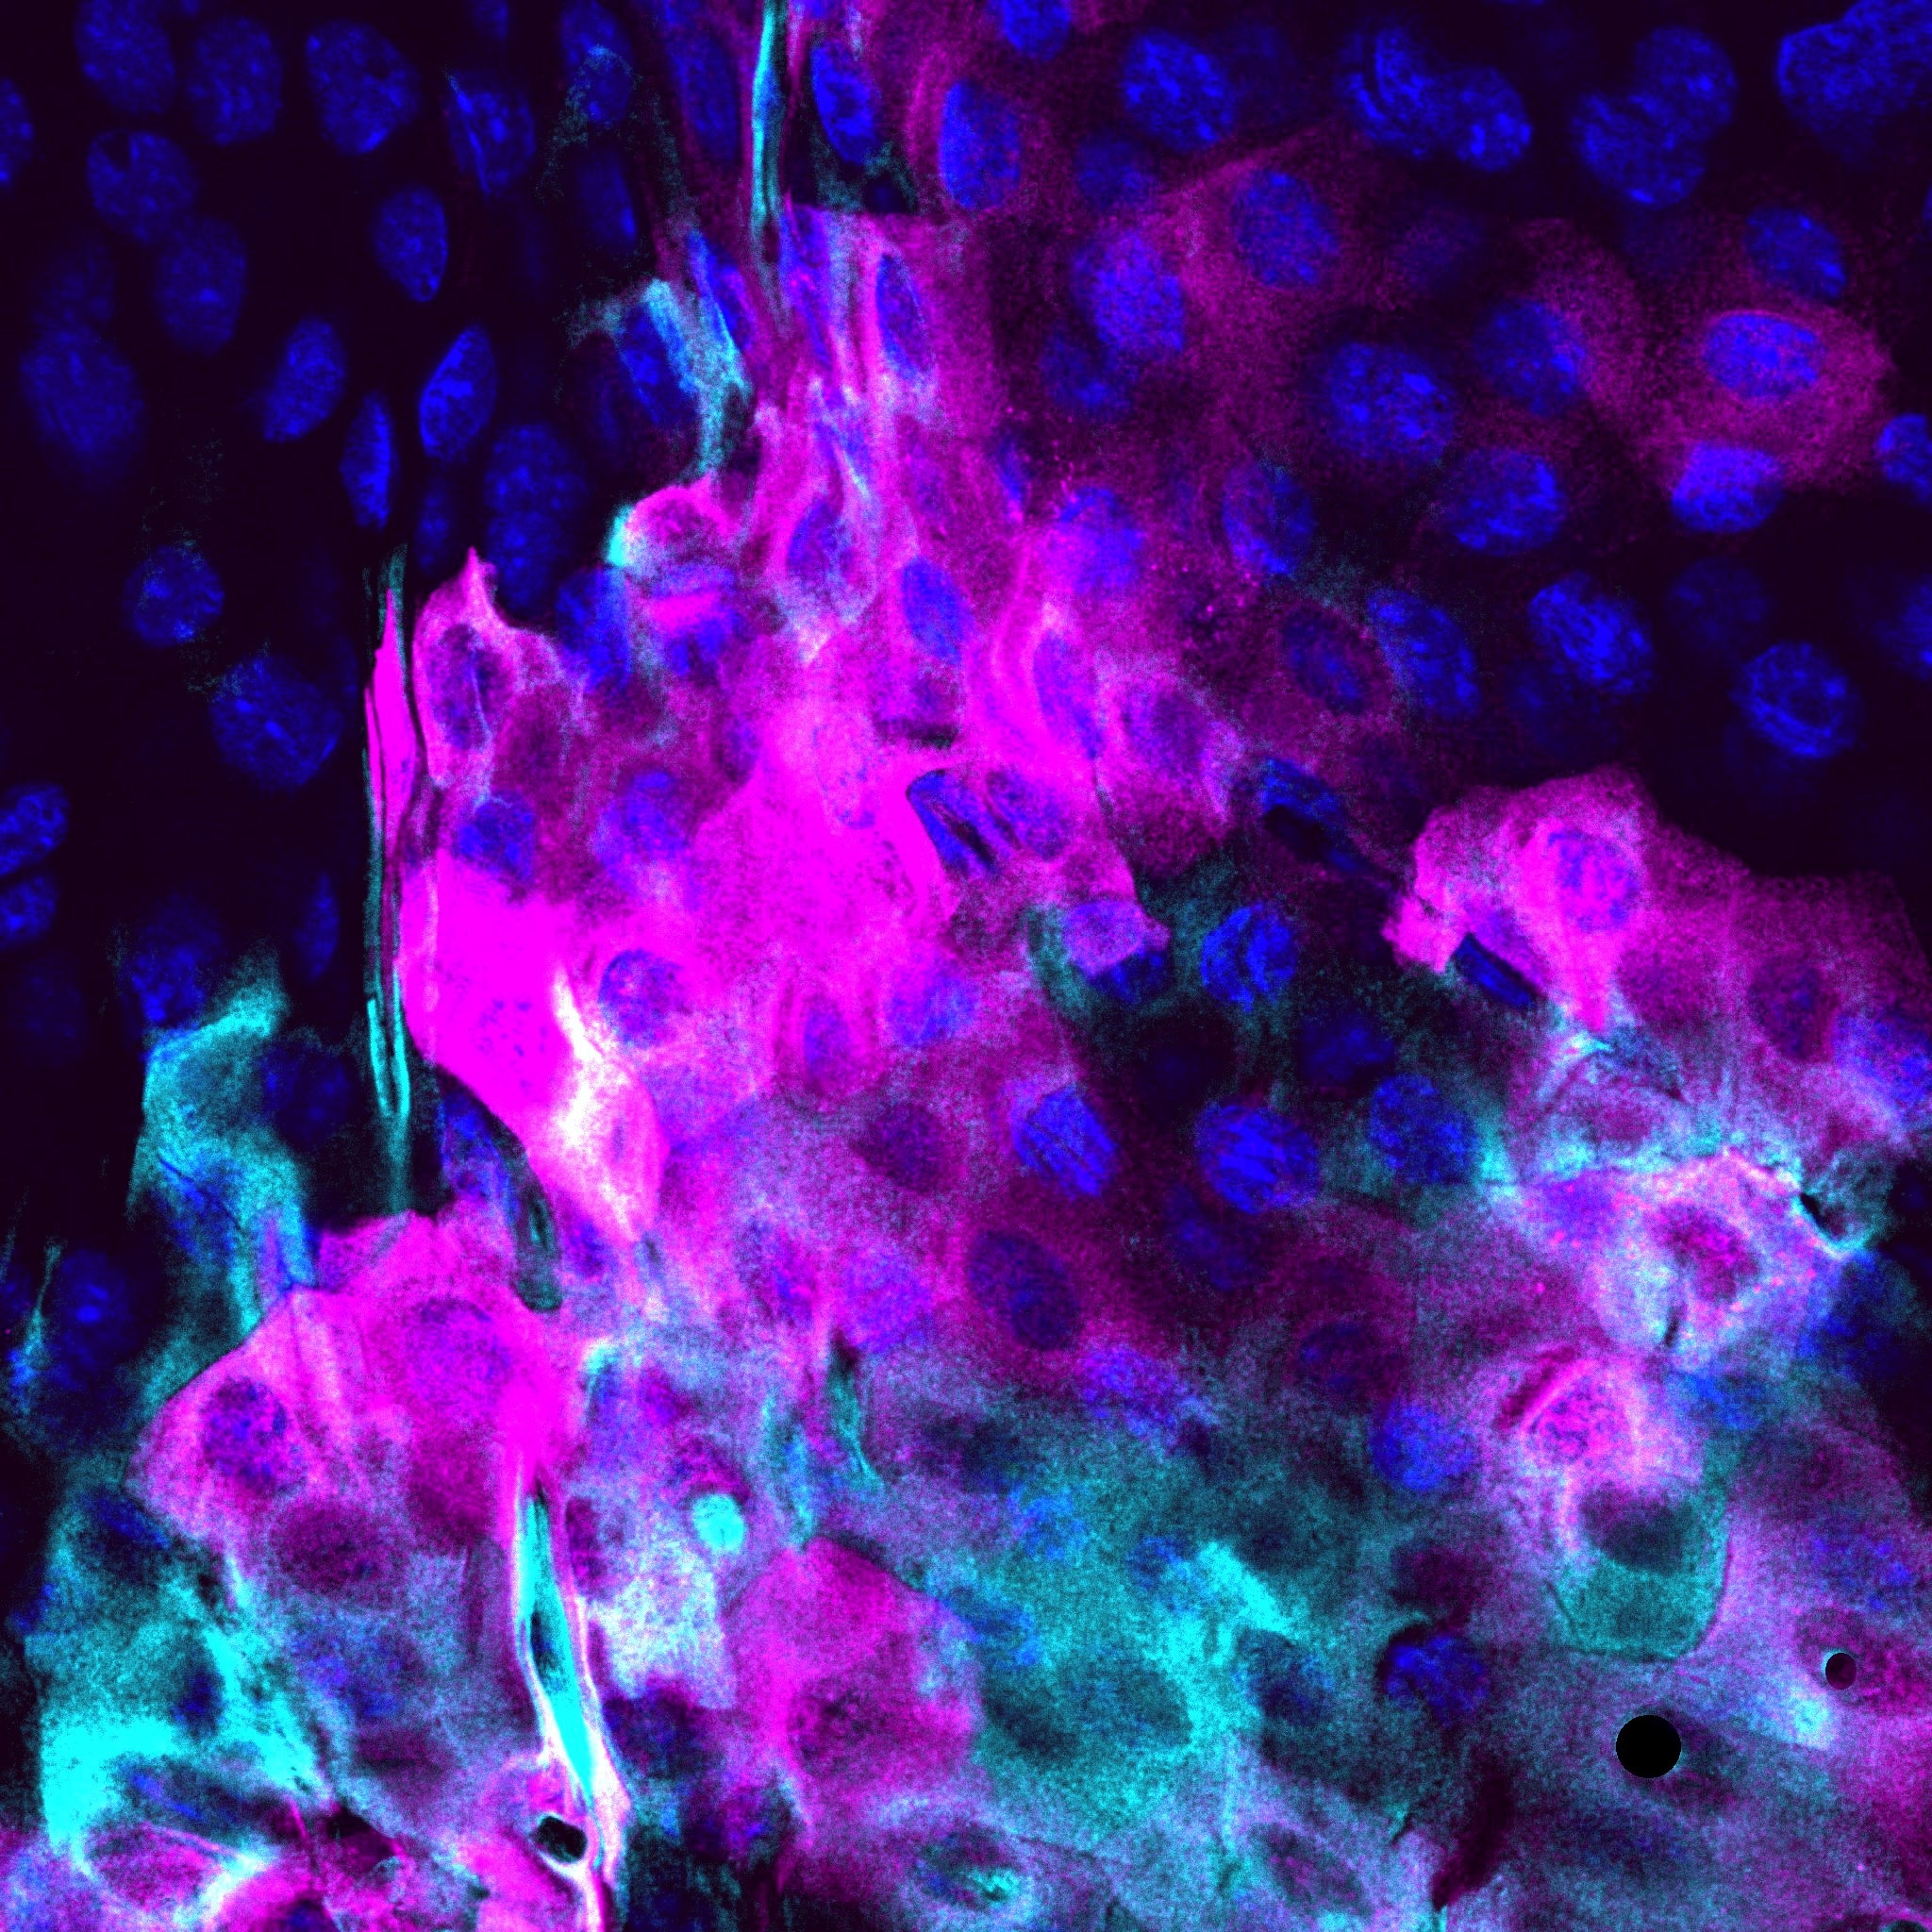

Thai Hong Anh Tran

Honours Student

UNSW School of Biomedical Sciences

z5422352@ad.unsw.edu.au

• Microscope: Zeiss LSM 900

This is a 400x original magnification image showing the staining pattern of two biological markers located in the healthy conjunctiva, which is the thin layer covering the white of the eye and the inside of the eyelids. The magenta shows a novel gene currently under research, and the cyan shows Cytokeratin 8 (K8), a thread-like protein that gives conjunctival cells their shape and strength.

K8 is one of many biomarkers clinically used to diagnose conjunctivalisation, a disease process where abnormal tissue from the conjunctiva grows over the cornea, resulting in blindness. Unfortunately, these biomarkers are not always reliable for clinical diagnosis as they can also be found on other areas of the eye or be naturally present under healthy conditions. In our study, we found that the novel biomarker (magenta) appears on diseased corneal tissue of mice but not in their healthy corneal tissue. This specificity could be key to identifying the mechanism driving conjunctivalisation and allow for better patient outcome by providing earlier diagnosis and therapeutic interventions.

Artistically, these colours evoke the image of a fire burning in the rain - a reminder that even under diseased conditions, nature continues to shine. In the same way, we too can choose to shine in the face of scientific challenges, letting persistence light our path towards discovery.